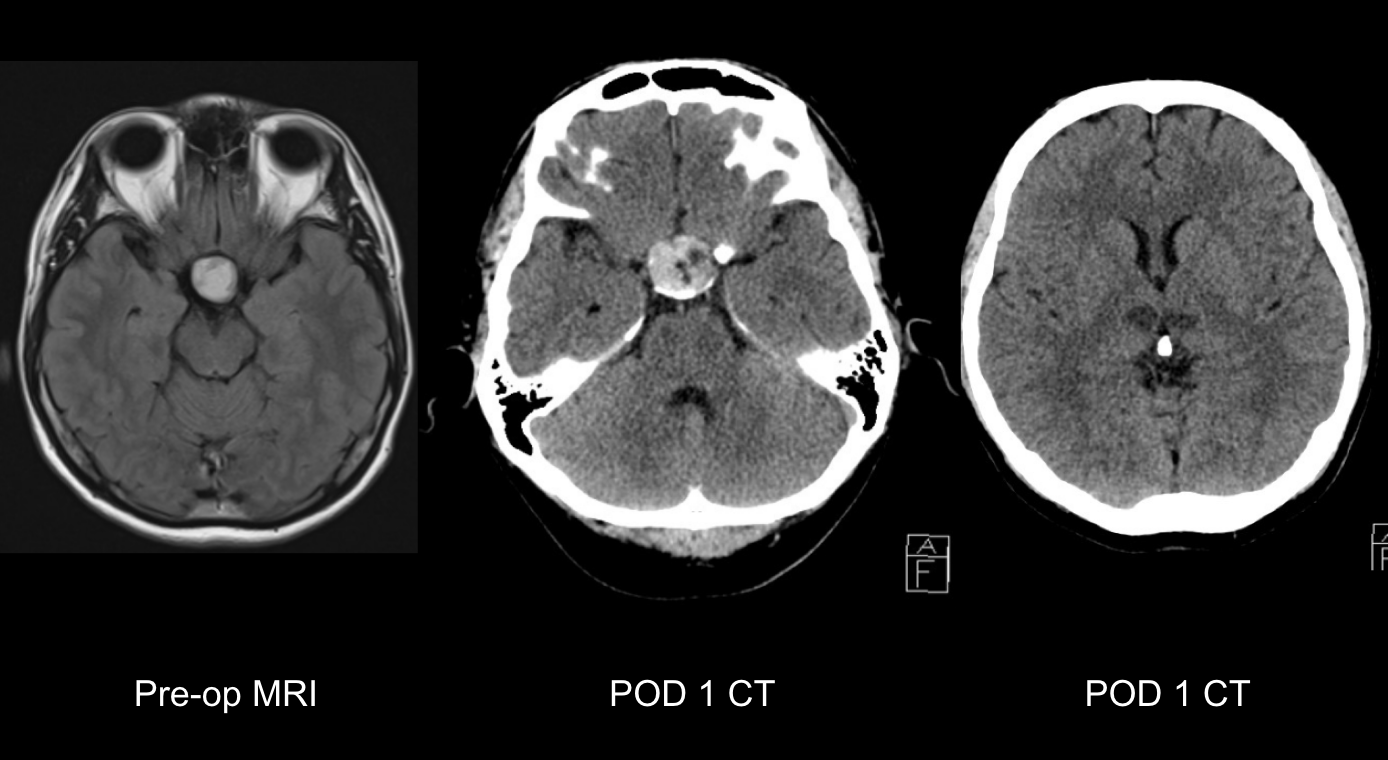

Cnsf trial total enroll

Cnsf design 1

Design of all RCTs

Cnsf outcomes summarized

CONCLUSION

Better recanalization rates are seen with TNK in ETW, but may not be associated with improved functional outcomes at 90 days compared to medical management. Incidence of sICH also remains largely favorable, except in TRACE 3, which showed a higher incidence in the TNK group. There remains a need for more RCTs in this population.

Trial

LVO

EVT Access

Recanalization

Functional Outcome

sICH

TIMELESS

Yes

TNK group: ↑

No difference (mRS=3)

Similar

CHABLIS-T II

TRACE 3

No

N/A

TNK better (33% vs. 24.2%)

Increased in TNK group (3% vs 0.8%)